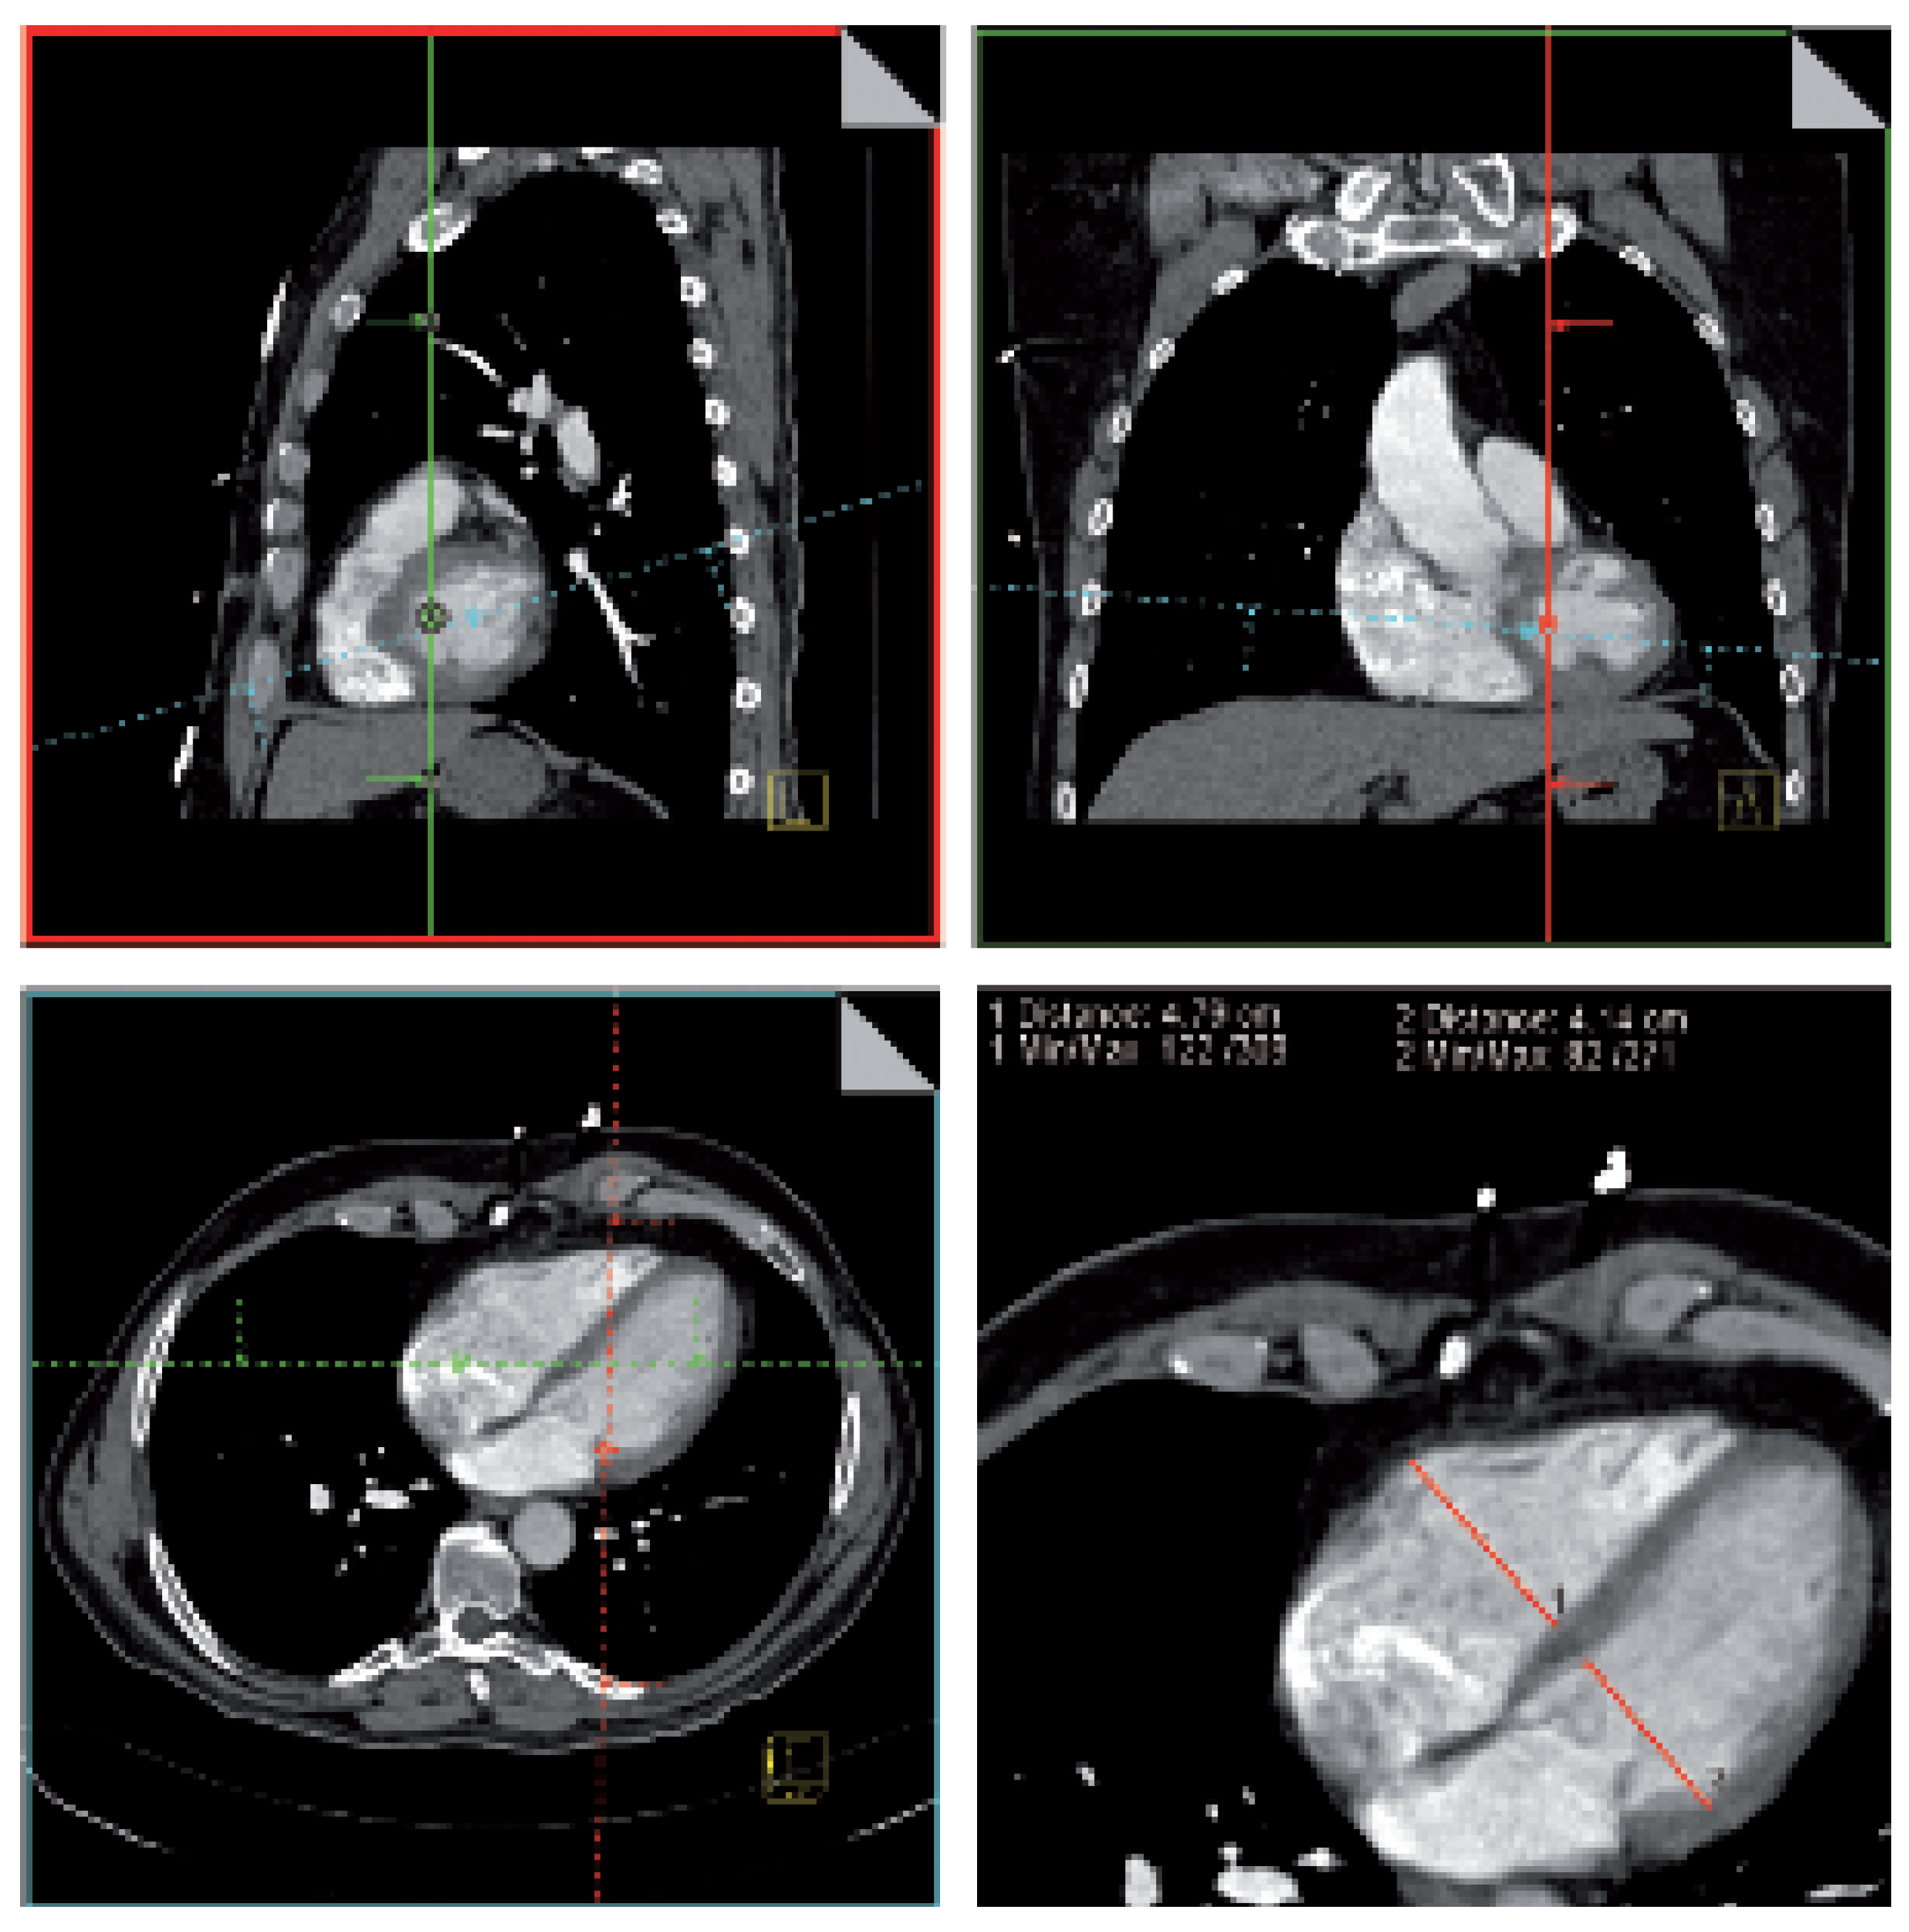

Contrast enhanced chest computed tomography (CT) is increasingly used as the first-line PE imaging test and is available around the clock at most institutions. With newer generation scanners, standardised cardiac views are easily obtained in almost all patients who undergo contrast-enhanced chest CT. Most contemporary CT scanners allow online twodimensional reconstruction of standardised cardiac views, with direct measurement of ventricular dimensions (Figure 5). In the reconstructed four-chamber view, right (RVD) and left ventricular dimensions (LVD) are then measured by identifying the maximal distance between the ventricular endocardium and the interventricular septum, perpendicular to the long axis of the heart. Right ventricular enlargement is defined as RVD/LVD >0.9.

In 63 patients with acute PE, the presence of right ventricular enlargement on the reconstructed CT four-chamber view correlated with the presence of right ventricular dysfunction on echocardiogram [11].

Right ventricular enlargement on chest CT helps identify patients at risk of death from right ventricular failure. In a study of 431 consecutive patients with acute PE, right ventricular enlargement on the reconstructed CT four-chamber view was an independent predictor of 30-day mortality after adjustment for important patient characteristics (Figure 6) [12]. Prospective management studies are needed to investigate whether cardiac measurements on reconstructed CT 4-chamber views are useful to guide treatment decisions in patients with acute PE.

Figure 5. Multiplanar reconstruction of the CT four-chamber view with measurement of right and left ventricular dimensions. In the sagittal view (A), the viewport (dashed line) is rotated counterclockwise to obtain a craniocaudal axis. After tilting the viewport (dashed line) slightly clockwise in the coronal view (B), the four-chamber view (C) is obtained. Measurement of right and left ventricular dimensions in the reconstructed four-chamber view is shown in panel D.